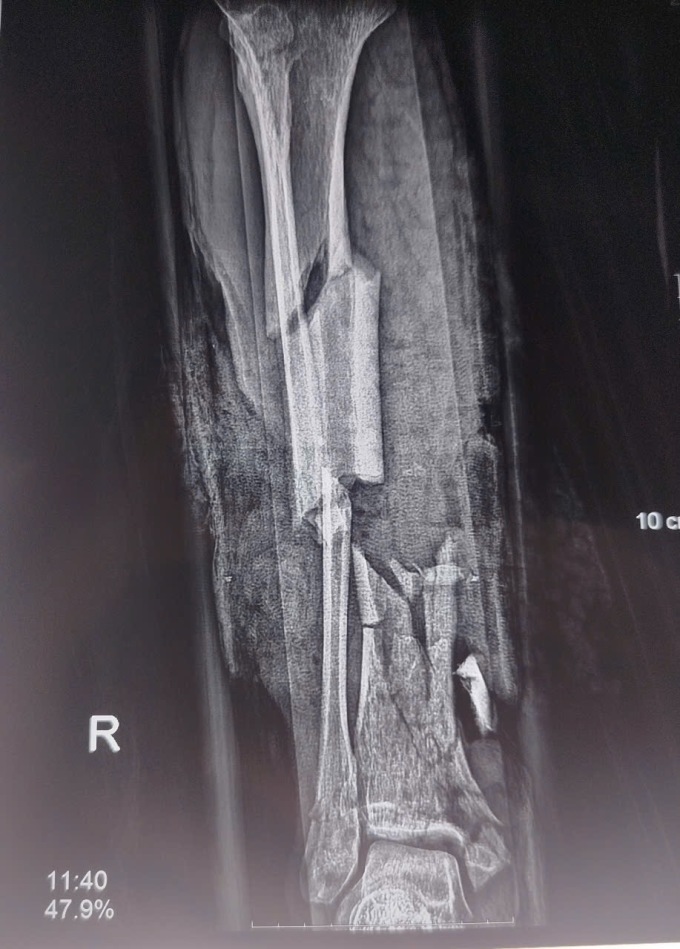

Phim chụp chân tổn thương do nổ bình gas. Ảnh: Bệnh viện cung cấp